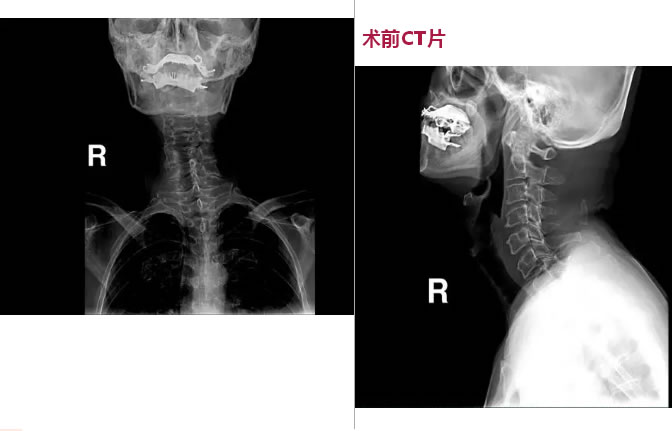

果然通过体查、颈椎DR、颈椎MR、颈椎CT,发现他有多节段颈椎间盘突出,颈椎管狭窄,相应水平的颈髓受压,脊髓水肿变性,符合脊髓型颈椎病的诊断。肖隆艺认为,在脊髓受到压迫的情况下,骆先生从事超市服务工作,整天低头也会加重症状。

术前CT片